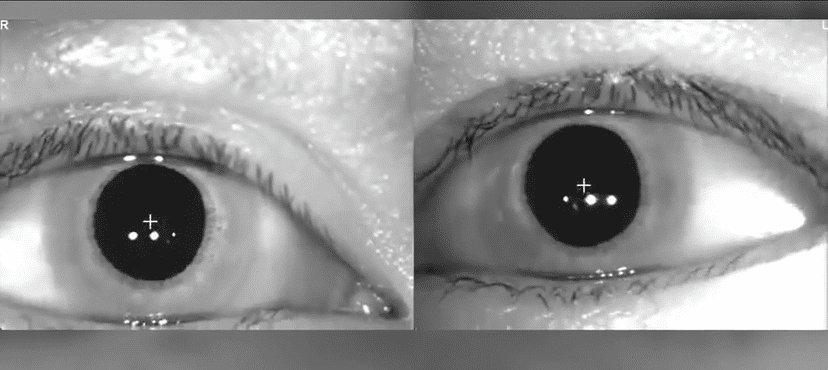

Nystagmus, that involuntary rhythmic eye movement, often seems singular. However, it's a complex interplay of two distinct phases: slow and fast. While we typically name nystagmus based on the direction of the fast phase, understanding the slow phase is crucial for clinicians like physical therapists specializing in vestibular disorders. This article will delve into the intricacies of these two components and explain why the slow phase is often referred to as the 'vestibular response.' We will also discuss the nuances of interpreting the fast phase and its clinical implications, presenting a stimulating challenge for clinicians in the diagnostic process.

The slow phase of nystagmus is the direct result of vestibular stimulation. Think of it this way: your inner ear's vestibular system detects head movements and sends signals to your eyes to keep your vision stable. When your head moves, the vestibular system triggers a reflex that moves your eyes slowly in the opposite direction of the head movement. This counter-movement helps maintain your gaze on a fixed point while your head is in motion. This slow movement is the slow phase of nystagmus and directly reflects the vestibular system's activity. Therefore, it is often called the vestibular response.

The slow phase can't continue indefinitely. If it did, your eyes would eventually roll entirely out of their sockets! This is where the fast phase comes in. It's a quick, corrective jerk of the eyes back to the center (or to a new fixation point). This rapid movement is what we see and is what gives nystagmus its characteristic jerky appearance. It is a repositioning saccade—a fast, corrective eye movement similar to the saccades we make when quickly shifting our gaze from one object to another. This fast phase is generated by neural circuitry in the brainstem, not simply recoil from stretched eye muscles.

So, in an example of the head-turning right, they will quickly jerk back to the right after the eyes have slowly moved to the left. This quick rightward movement is the fast phase.